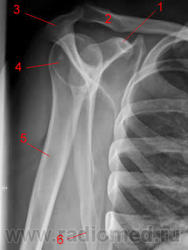

Киста головки плечевой кости

Пятничный случай: под закрытие пришла женщина, 65 лет, жалобы на боли в области левого плечевого сустава при движении, со слов больной "всю жысть". Отправлена хирургом с предположительным Ds: артроз левого плечевого сустава.

Вот я думаю написать: в области головки левой плечевой кости определяется округлое просветление в костной ткани диаметром 48 мм с четкими контурами, окружено остеосклерозом. Кортикальный слой области просветления истончен.

Заключение: костная киста головки левой плечевой кости (?), диф. Ds: энхондрома. Консультация онколога.

Это головка плечевой кости в ортопроекции.

Так, для интересу.

Область плечевого сустава.

Рис. 1. 1, Ключица. 2, Акромион. 3, большой бугорок. 4, малый бугорок. 5, хирургическая шейка. 6, плечевая кость. 7, клювовидный отросток;. 8, латеральный край лопатки. 9, Ребро.